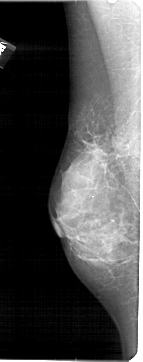

A_1431_1.LEFT_MLO

LEFT_MLO LINES 5416 PIXELS_PER_LINE 2131 BITS_PER_PIXEL 12 RESOLUTION 43.5 NON_OVERLAY